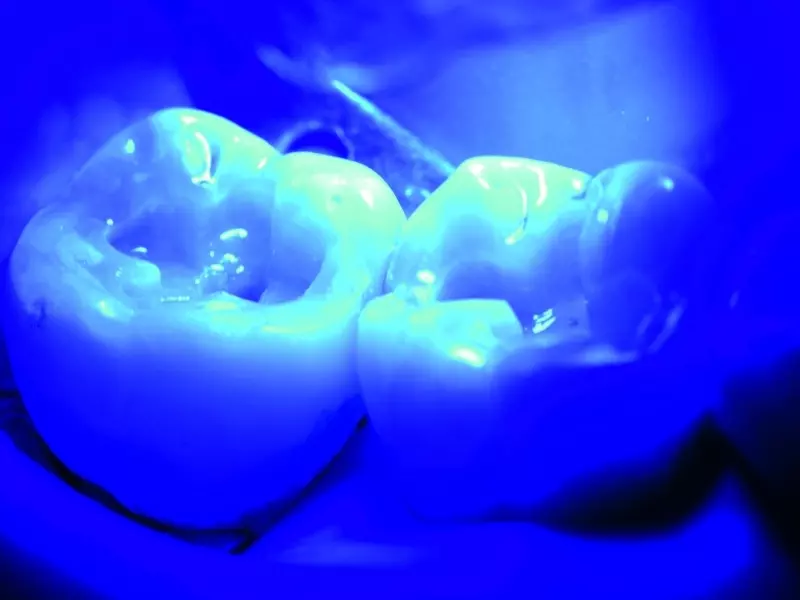

Nanohybrydowy materiał odtwórczy typu ORMOCER® Admira Fusion x-tra okazał się korzystnym rozwiązaniem w przypadku odbudowy w odcinku bocznym. Poza takimi zaletami, jak łatwość pracy, dobre parametry podczas zakładania i wyjątkowa polerowalność, charakteryzuje się również możliwością uproszczenia techniki odbudowy – pozwala wykonywać głębokie i rozległe odbudowy w znacznie krótszym czasie niż w przypadku tradycyjnych materiałów i technik odbudowy. Jest to możliwe jedynie dzięki temu, że materiał wykazuje dużą głębokość polimeryzacji światłem (do 4 mm) i niski poziom skurczu polimeryzacyjnego, zmniejsza naprężenia powstające pomiędzy powierzchniami łączonymi adhezyjnie, a dodatkowo zapewnia uzyskiwanie wypełnień o optymalnej jakości.